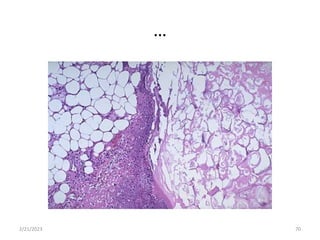

Fat necrosis

…